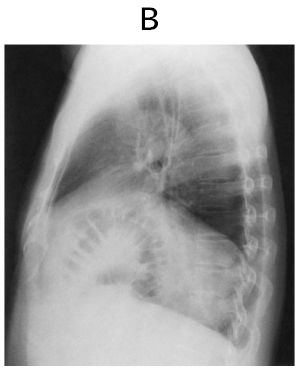

胸部エックス線写真の正面像(別冊No.5A)と側面像(別冊No.5B)を別に示す。

- 画像(別冊)では左横隔膜の挙上が予想される。

→ 高齢者に多い横隔膜弛緩症(diaphragmatic eventration)が最も一致。

- 胸部X線やCTで横隔膜の挙上と、時に腸管ガス像が見られる。